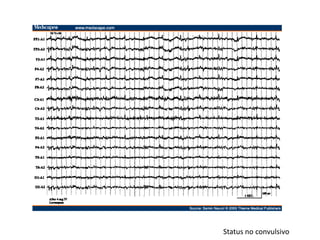

Este documento presenta información sobre la epidemiología, clasificación, etiología y tratamiento de las convulsiones y epilepsia. Se describen varios síndromes epilépticos según las edades, incluyendo el síndrome de West, síndrome de Dravet, síndrome de Lennox-Gastaut y otros. También se discuten las crisis febriles, status epiléptico y niveles terapéuticos de medicamentos antiepilépticos comunes.